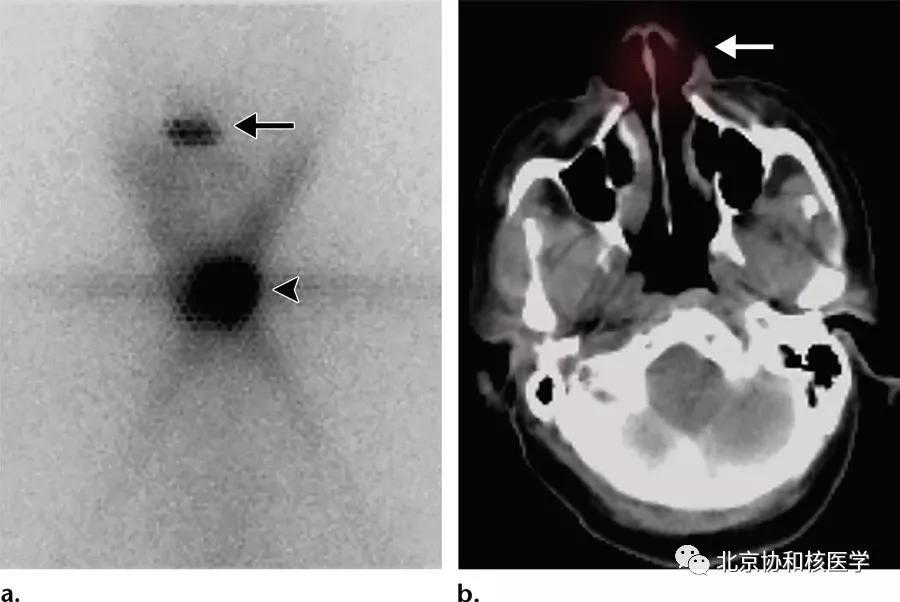

鼻腔息肉所致碘摄取,同时可见颈部残余甲状腺组织:

脑膜瘤所致碘摄取:

鼻骨骨样骨瘤所致碘摄取,腹部另可见由于巨大肾囊肿所致碘异常摄取: